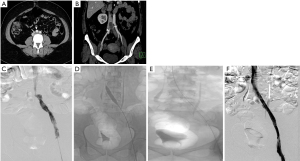

Unilateral swelling of the lower limb is commonly interrogated by physical examination aided by a venous duplex ultrasound of the affected limb. While color Doppler ultrasound is adequate and sensitive for the diagnosis of deep vein thrombosis and evaluation of varicose veins and venous incompetence, it is woefully inadequate to study the pelvic veins, especially the ilio-caval region. If the ultrasound is able to visualize the proximal CIV, it may demonstrate the lack or reduction of phasic variations of blood flow distal to the stenosis and turbulence (color mosaic) at the site of stenosis (Figure 1). The opposite side serves as a control. Venous collaterals, an important component of the diagnostic findings are poorly identified by ultrasound.

MDCT venography demonstrates the compression of the LCIV by the RCIA, presence of bony spurs, deep vein thrombosis, and pelvic venous collaterals and helps in the exclusion of other compressive pathologies (Figure 2). Patients with suspicion of pulmonary embolism can also undergo a CT pulmonary angiogram in the same sitting. Jeon et al. (18) proposed a morphological classification based on CT venography which included 3 types—type 1 was focal compression of the iliac vein by the artery, type 2 was diffuse atrophy of the iliac vein up to its formation, and type 3 was a thin, cord-like iliac vein in its entire length. This classification has a bearing on the treatment strategy as the fibrotic ones pose a challenge for balloon dilatation prior to stent placement.

MR venography, though uncommonly done for diagnosing MTS, is as accurate as CT in diagnosing the vascular compression, deep vein thrombosis and pelvic venous collaterals. In addition to the post contrast MR venography study (Figure 1), a time-of-flight (TOF) sequence (Figure 1) may identify flow reversal in the internal iliac vein (as such, no signal on 2D TOF) ipsilateral to common iliac vein compression and enlarged ascending lumbar vein in case of a tight iliac stenosis (19). Newer techniques like 4D flow MR venography may provide interesting insights into the flow dynamics like velocity and direction with superior temporal resolution in these patients; however there is lack of comprehensive evidence (20,21). One disadvantage of extracellular MR contrast agents is that they behave like iodinated contrast media with limited time window for imaging and need for repeat contrast administration if the initial imaging is suboptimal. This apparent glitch can be overcome by using blood-pool contrast agents (BPCA) which can remain in circulation for prolonged periods and thus allow a reliable and repeatable examination (22). Gadofosveset trisodium (Ablavar®, Lantheus Medical Imaging, North Billerica, MA) is the most commonly used BPCA for venous imaging. Another agent that has been used as a blood-pool contrast off-label is Ferumoxytol, a superparamagnetic intravenous iron supplement, FDA approved for patients with anemia of renal failure. The contrast effect is due to the strong shortening of T1 and T2* by the iron supplement. Circulation times are longer owing to its larger size and carbohydrate coating, making it suitable as a blood pool agent.

In the past decade, intra-vascular ultrasound (IVUS) has steadily found increasing use in the diagnosis and management of MTS. During the interventional procedure, IVUS can help in documenting and localizing the cause of iliac venous obstruction—spurs and intimal lesions from chronic adherent thrombus. It can also show the dynamic compression by the overlying artery (Figure 1). In addition to helping in re-canalizing the chronic occlusion, it can assess response of MT lesion to angioplasty and stent placement (Figure 1) and presence of residual thrombus thus aiding in continuation of lysis.

Catheter venography has traditionally been considered the gold standard for diagnosis of MTS. However due to its invasive nature, it is nowadays reserved for cases in which endovascular intervention is planned or diagnosis by non-invasive modalities is equivocal. Venography can demonstrate acute thrombosis within the iliac vein or the ilio-femoral veins. Chronic cases are associated with stenosis or occlusion of LCIV with pelvic and retroperitoneal collaterals (Figure 1) and flow reversal in ipsilateral internal iliac vein. Hemodynamic pressure gradient measurement is a valuable adjunct in confirming presence of significant stenotic lesion associated with MTS. May and Thurner (6) advocated measurement of pressure difference between the iliac veins (2 mmHg at rest, 3 mmHg during exercise), whereas Ferris et al. (26) advocated any gradient between the IVC and left iliac vein for diagnosis of hemodynamically significant obstruction.

Patients with isolated iliac vein thrombosis (minority) can have an ipsilateral common femoral venous access for the procedure. More commonly though, the femoral and popliteal veins are simultaneously involved along with the iliac vein, requiring a popliteal venous access. The choice of sheath size depends on the technique of recanalization. Various catheters (e.g., Indigo, Penumbra, USA) and lytic agents (Alteplase or Urokinase) can be used based on operator preference. During catheter directed thrombolysis, the sheath is flushed with heparin as a continuous infusion. Once there is near total or reasonable recanalization, the underlying stenosis at the iliac venous segment can be unmasked (Figure 2). Caution should be exercised in grading venous stenosis during venography as the iliac vein is compressed or flattened anteroposteriorly leading to a “pancake” effect on the angiographic image in the frontal projection (29). Various oblique projections may be needed for accurate estimation of stenosis. Intravascular ultrasound (IVUS) can help in locating and grading the stenosis. An appropriately long balloon of 8 mm or 10 mm diameter is used to perform an initial angioplasty (Figure 2). The results of angioplasty alone are traditionally below par when compared with stenting, irrespective of the post angioplasty result (30). At this point, an IVUS can help assess the response to plain balloon angioplasty and confirm the landing zones for the stent if required. Self-expanding, Stainless steel stents (Wallstent, Boston Scientific, USA) are preferred, because of their higher radial force, long length and flexibility (Figure 2). However, these stents come with niggles of their own; difficulty in precise placement and possibility of foreshortening being a few. As a principle, balloon mounted stents should be avoided as they can be deformed by the arterial pulsation. Multiple stents should also be avoided as they increase the incidence of in-stent stenosis (31). The primary patency rates at 1 year and 5 years were 93.2% and 74.5% respectively and the secondary patency rates at 1- and 5-year at 100% and 92% respectively in one single center experience (31). The 6-year primary patency rate of iliac venous stents is close to 79%, which exemplifies the role of stenting in this setting (32). The distal (downstream) landing zone is still a debatable topic (33). The Wallstent, being a braided stent, is weakest at its ends and this makes the stent vulnerable to being crushed by the culprit RCIA. Hence the interventionists overcome this by landing it in the lowermost vena cava apposing the right lateral wall. But the problem with this technique is it induces a pseudo-intima formation over the caged right common iliac vein surface of the stent resulting in increased incidence of venous thrombosis on the covered side. Newer dedicated laser-cut nitinol venous stents such as the VICI (Boston Scientific) (Figure 1) (34) and VENOVO (Bard) (35) stents have high patency rates and excellent precision at the time of deployment. These stents have higher resistive radial strength preventing the collapse or crushing of the stent by the right common iliac artery and hence can be deployed flush with the ostium of the LCIV. Following the procedure, patients are switched to oral anticoagulation for a period of 6 months and low dose aspirin thereafter. The choice of oral anticoagulation post endovenous therapy is not adequately evaluated in literature. A systematic review of the studies examining endovenous therapy for MTS, revealed that warfarin has been the most commonly used anticoagulant (36). The newer oral anticoagulants, apart from being equally efficacious, certainly have benefits over warfarin including reduced bleeding complications and avoidance of periodic monitoring. Periodic follow up with ultrasound or CT venography at 1, 3, 6 and 12 months and thereafter yearly for stent patency and symptomatic recurrence is important for early diagnosis of stent occlusion and retreatment. Treatment failures are very rare unless there is residual stenosis anywhere in the dilated/stented segment, incomplete clot clearance, suboptimal inflow from femoropopliteal veins or noncompliance to optimal anticoagulation. An immediate treatment failure in the form of acute stent re-thrombosis is addressed with a relook endovenous therapy with correction of the causative factor. Delayed presentation with stent occlusion is approached according to the clinical findings. If the symptoms are subacute or chronic, of mild severity, usually after cessation of anticoagulation, with well collateralized stent occlusion, then a conservative strategy with reinitiation of lifelong anticoagulation is advised. Alternatively, if there is acute onset severely symptomatic venous thrombosis, a repeat endovenous intervention is preferred.